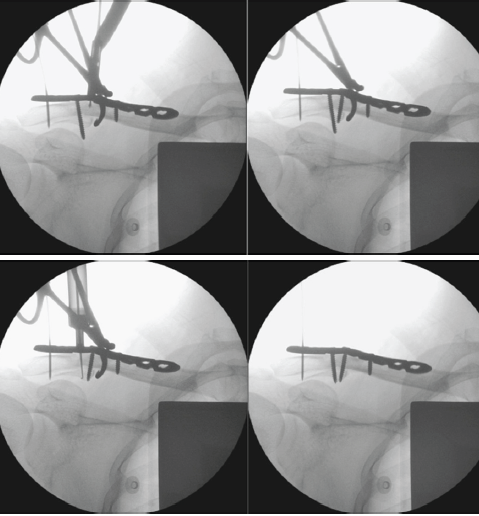

Once the plate has been securely applied and the remaining screw holes secured, the 3.5 mm cortical screw was then replaced with an appropriately sized cortical screw (holding screw) that engages the inferior fragment (Figs. 4 and 5).

Figure 4: Replacement of a 3.5 mm cortical screw with an appropriately sized holding screw.

Figure 5: Final plate and screws placement engaging the inferior fragment.